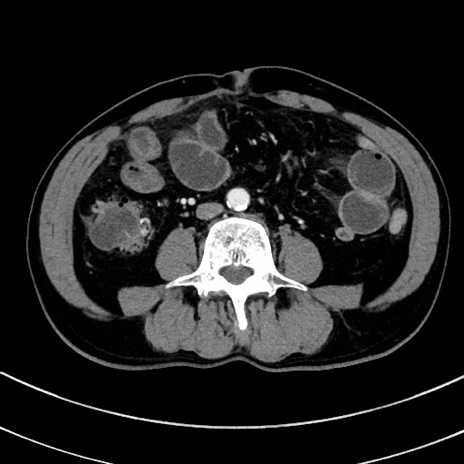

冠状断像

【症例】 60歳代男性

【主訴】 黒色吐物

【現病歴】 4日前から嘔気自覚、2日前の朝食後にも嘔気あり、自分で手で嘔吐反射起こし嘔吐したところ血が混ざっていたため受診。

【既往歴】 5年前汎発性腹膜炎を伴う急性虫垂炎で手術、高血圧、前立腺肥大症、高脂血症

【身体所見】 腹部正中に手術癩痕あり 腹部平坦・軟圧痛なし膨満感あり

【データ】WBC 8400、CRP 4.54